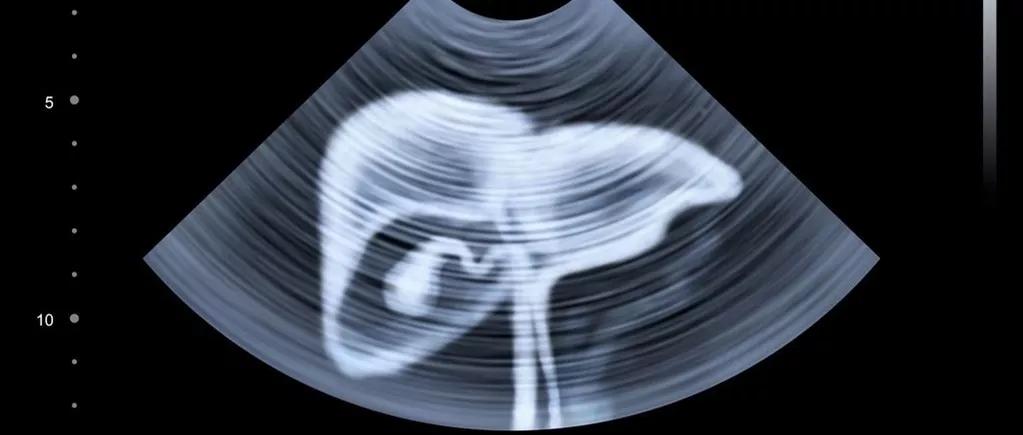

乙型肝炎病毒——原发性肝癌

乙型肝炎病毒(HBV)会增加肝癌的发生率,这是医学界普遍明确的结论。如果监测不到位,不仅患者可能进入“肝炎-肝硬化-肝癌”的恶性进展中,其家人也有可能染病。